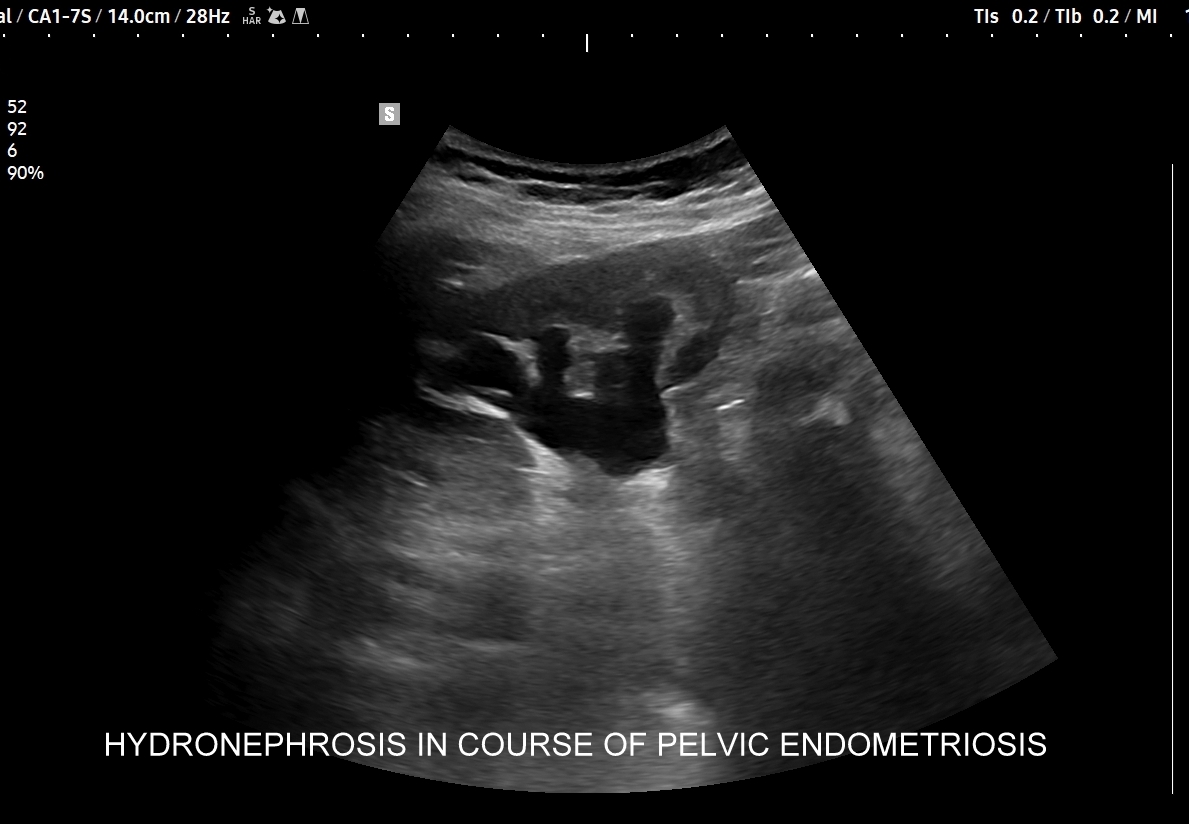

W badaniu USG ogniska endometriozy zwykle przyjmują formę hypoechogennych guzków i nieregularnych mas; mogą być niejednorodne echogenicznie i zawierać drobne obszary torbielowate; w trybie color-Doppler i MVI wykazują skąpe unaczynienie.

Na skanach w niniejszym artykule zaprezentowany jest przypadek endometriozy głębokiej w miednicy mniejszej z intraluminalnym nacieczeniem dystalnego odcinka moczowodu, jego całkowitą niedrożnością i wtórnym wodonerczem. Choroba w tak zaawansowanym stadium wykryta została przypadkowo w rutynowym przezbrzusznym badaniu USG jamy brzusznej. W ramach diagnostyki różnicowej przeprowadzone zostały badanie CT, MRI oraz ureterocystoskopia z pobraniem materiału do badania histopatologicznego, na podstawie którego postawiono rozpoznanie endometriozy.